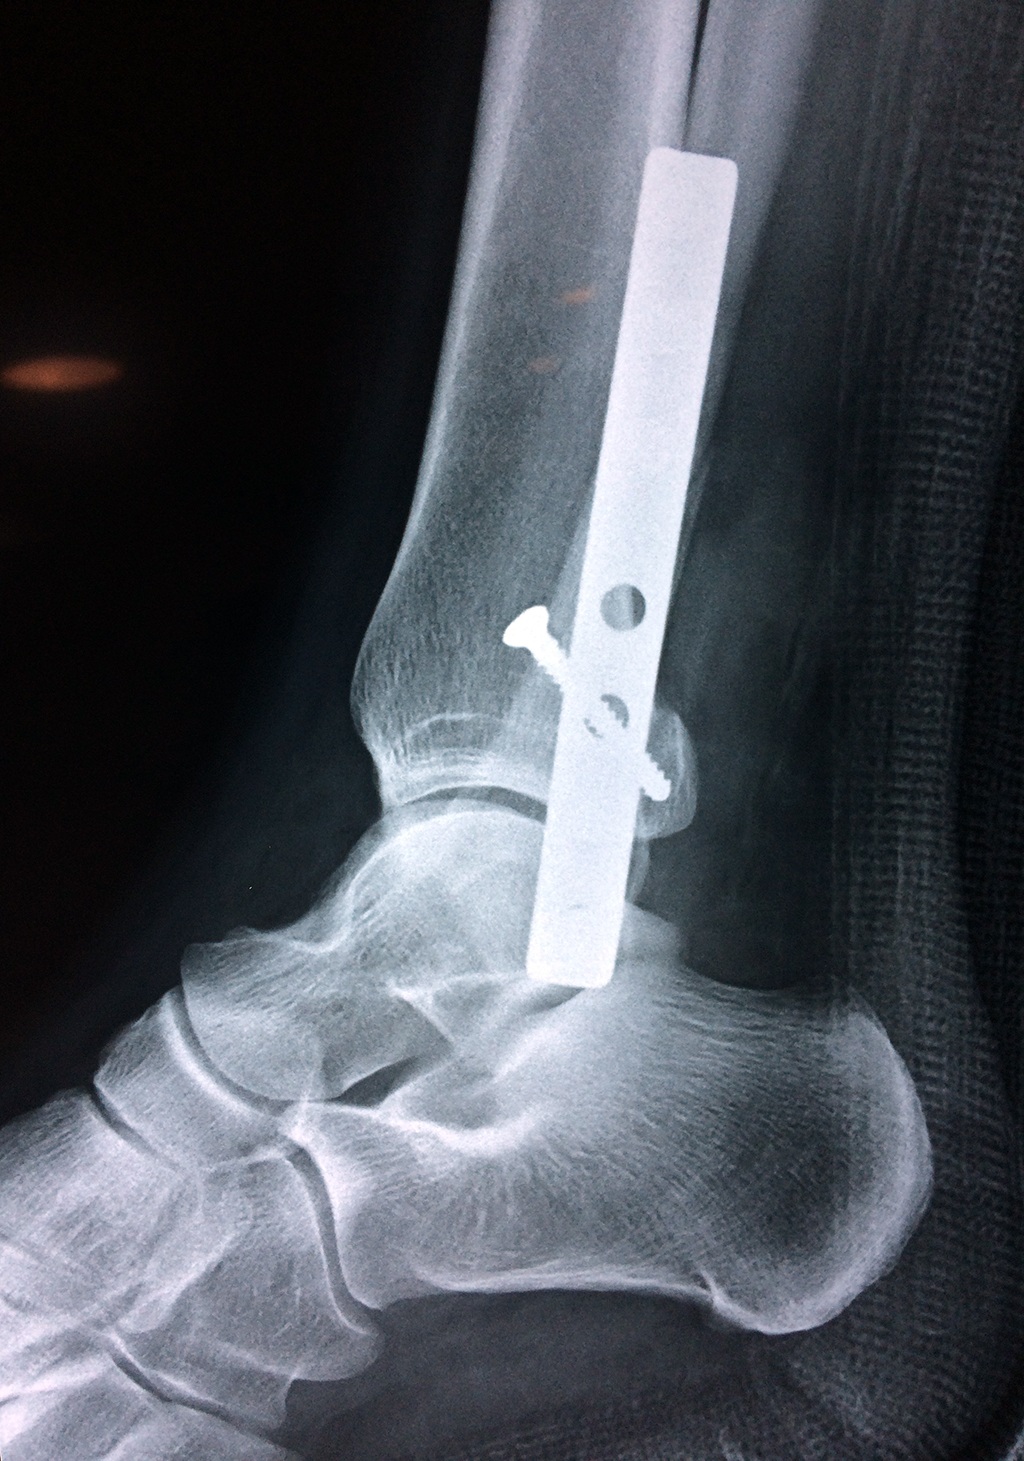

Cuando se necesita cirugía, es probable que esta implique el uso de clavijas de metal, tornillos o placas para sostener los huesos en su lugar mientras la fractura se consolida. Los elementos de soporte pueden ser temporales o permanentes.

Cirugía de Tobi...

Detail Download